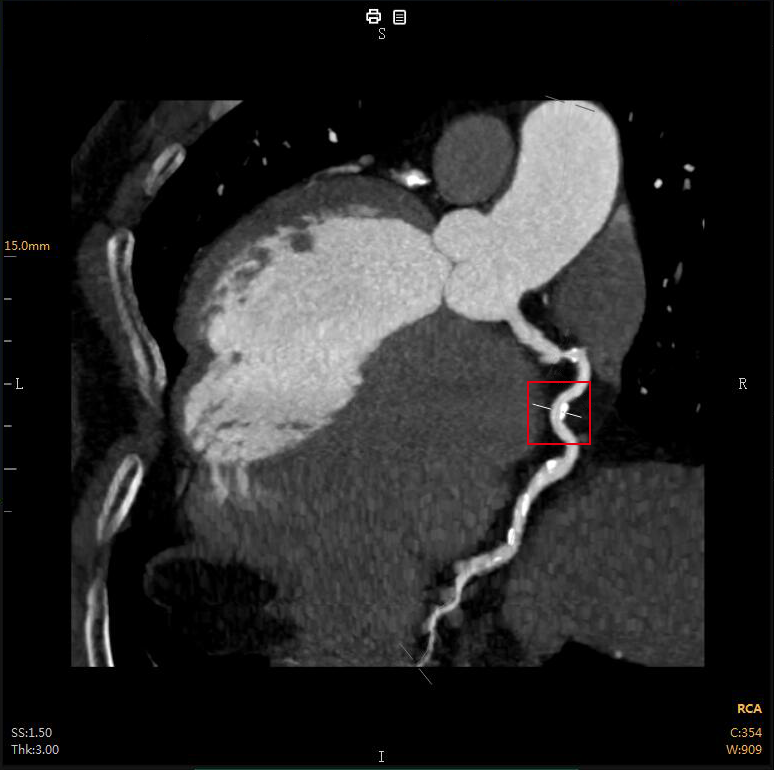

“CTA冠脈全自動(dòng)診斷”

Automatic Coronary Diagnosis

CTA冠脈動(dòng)脈造影以幾乎無(wú)創(chuàng )的方式

成為冠心病的首選檢查

全自動(dòng)圖像重建/分割

全自動(dòng)量化測量

云端AI的CTA冠狀動(dòng)脈全自動(dòng)診斷

重構了CTA冠脈檢查的極簡(jiǎn)流程